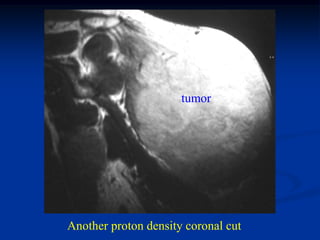

Case #263           Coronal proton density MRI

tumor

72 year female with MFH deltoid muscle

Another proton density coronal cut